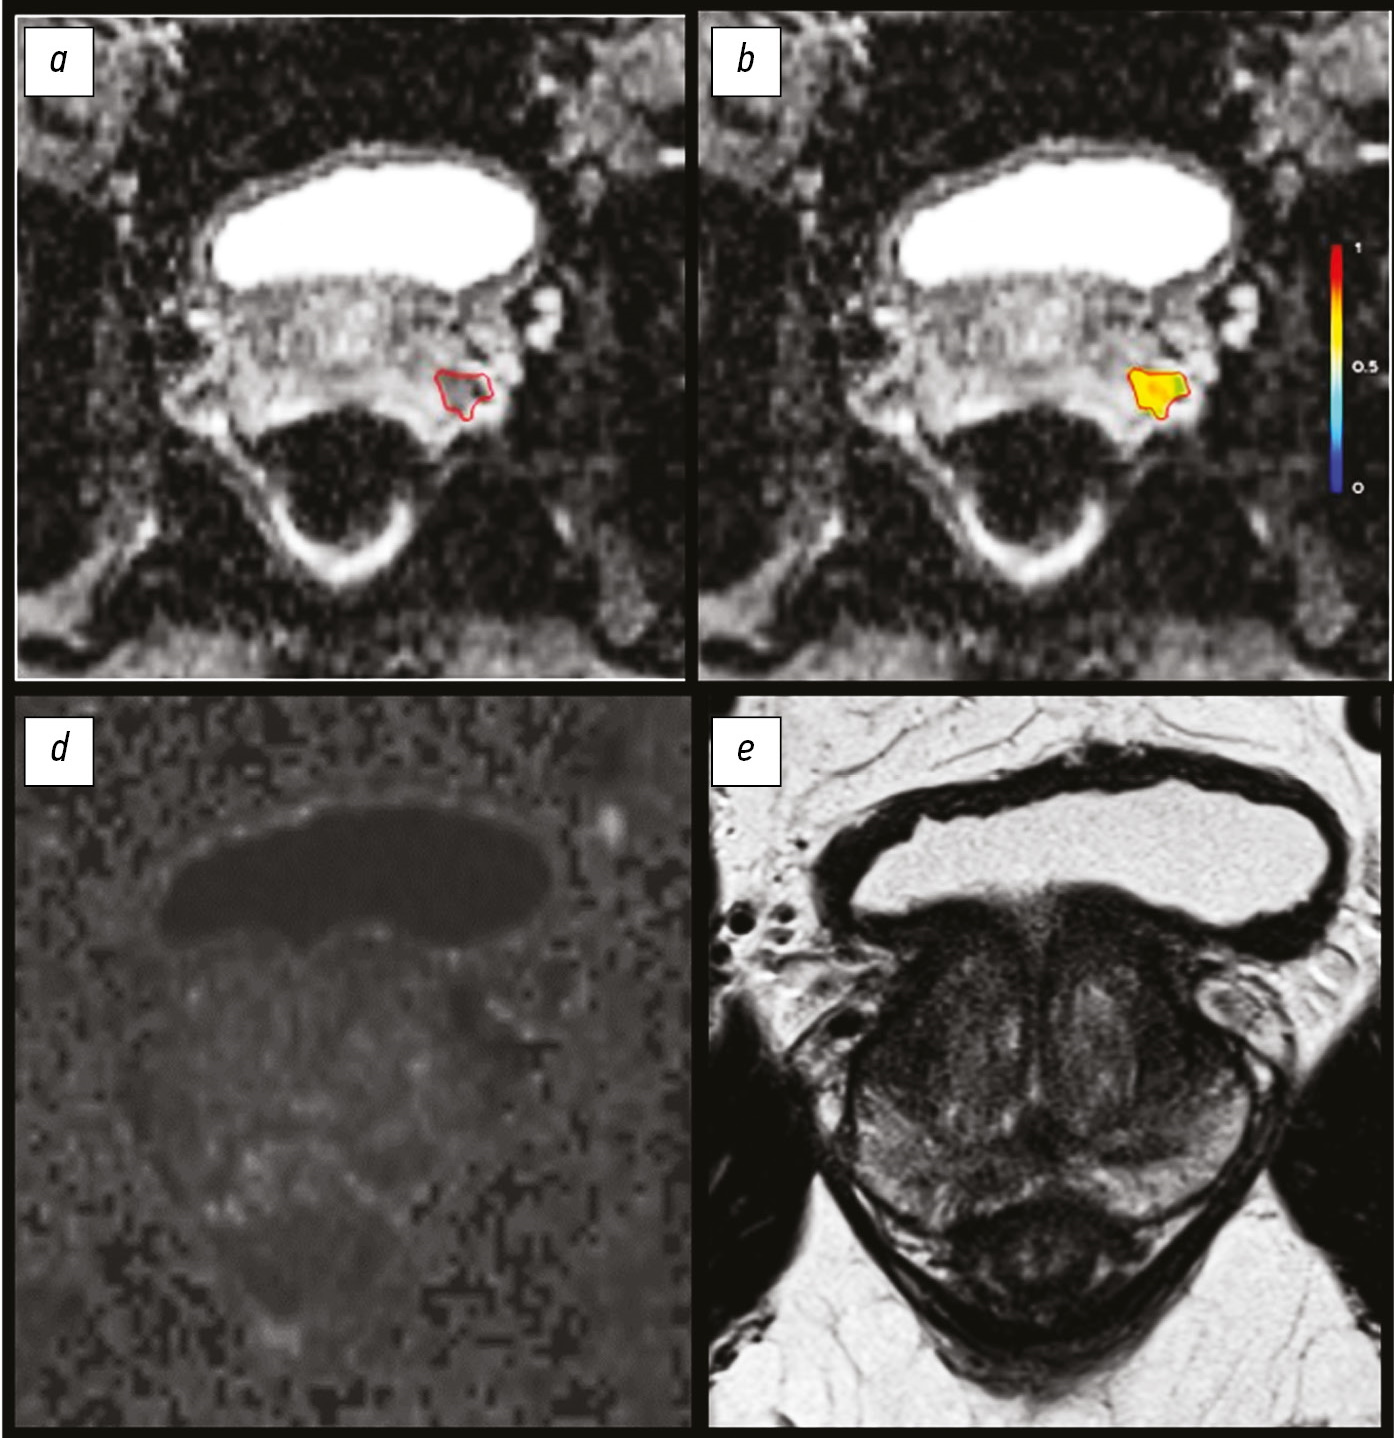

Материалы и методы. Ретроспективный анализ результатов исследований методом магнитно-резонансной томографии (1,5 Т) 156 пациентов с внемозговыми образованиями. Пациенты были разделены на 2 группы: (1) c наличием перифокальных изменений (n=106) и (2) внемозговым образованием без перифокальных изменений (n=50). В протокол сканирования были включены диффузионные и перфузионные последовательности. За зону интереса принимали (1) основной очаг и (2) зону перифокальных изменений. Выполнены измерения от основного очага и от зоны перифокальных изменений на картах измеряемого коэффициента диффузии, T2*-контрастной перфузии (DSС), проведен анализ серий динамического контрастирования (DCE).

Результаты. Максимальный размер основного очага (узла) поражения в 1-й группе составил 2,2 см (1,4; 4,3), во 2-й группе ― 1,2 см (0,9; 3,5); ограничение диффузии от основного очага поражения выявлено у 42 (39,6%) человек 1-й группы и у 7 (14%) ― 2-й. Максимальный размер перифокальных изменений в 1-й группе составил 2,85 см (1,5; 4,7). Ограничение диффузии от периферической зоны выявлено в 52 (49,1%) случаях. У пациентов 1-й группы с верифицированной менингиомой (n=66) путём многофакторного линейного регрессионного анализа выявлено, что максимальный размер основной зоны поражения увеличивал коэффициент объёмного кровотока (rCBF) от зоны перифокальных изменений в 3,3 раза (βcoef. 3,3, ДИ 1,27; 5,28; p=0,003), однако снижал показатель регионарного объёма крови (rCBV) в 4 раза (βcoef. 4, ДИ -7,46; -0,71; p=0,02).

Заключение. Перфузионные и диффузионные методы в сочетании с анатомическими последовательностями демонстрируют потенциал и могут выступать радиомическими маркерами при диагностике и лечении внемозговых образований. В дальнейшем наиболее перспективным выглядит выявление радиомических функциональных маркеров от зоны перифокальных изменений.